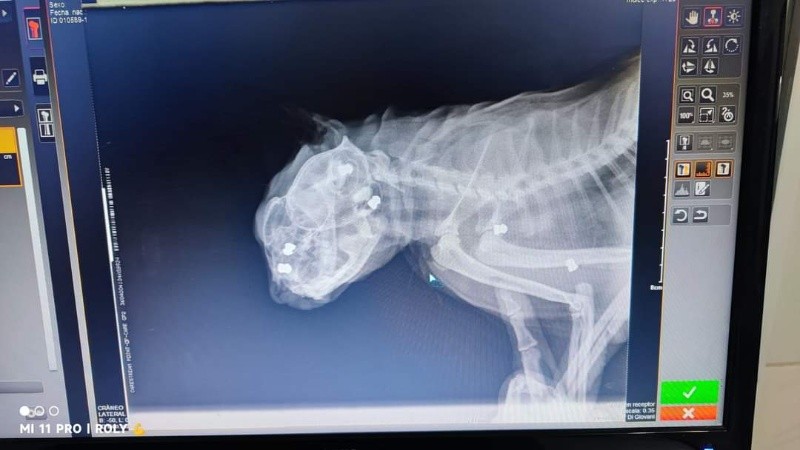

El hecho tuvo lugar en la zona de Cazadores al 2700. La gatita tuvo que ser atendida y los veterinarios no podían creer la brutalidad del ataque sufrido: la placa evidencia claramente los 6 impactos, 4 en el cráneo y los restantes en la parte del abdomen.

Según relató la mujer, el jueves pasado, el animal apareció en el patio herido: “Era toda sangre, le salía por el ojo, la boca, la nariy y el oído”, detalló. La familia rápidamente llevó a la gata a un consultorio veterinario donde le hicieron las primeras curaciones y fue derivada a otro consultorio en el que le practicaron una radiografía.